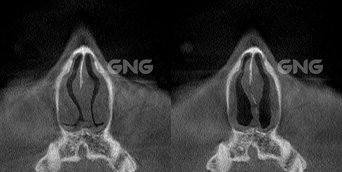

왼쪽 코의 코막힘 증상으로내원해주신 분입니다.코막힘 원인을 파악하기 위해 3D-CT를 촬영했는데요.아래 사진들을 보시면 비중격 만곡증 증상인휘어진 비중격의 모습을 육안으로 확인할 수 있습니다. 왼쪽에 뼈가 많이 튀어나와있고수술 후 해당 위치의 뼈가 제거되면서양쪽 비강, 특히 좁았던 왼쪽 부분이열린 모습을 볼 수 있습니다. <코막힘 원인> 수술 전, . . .